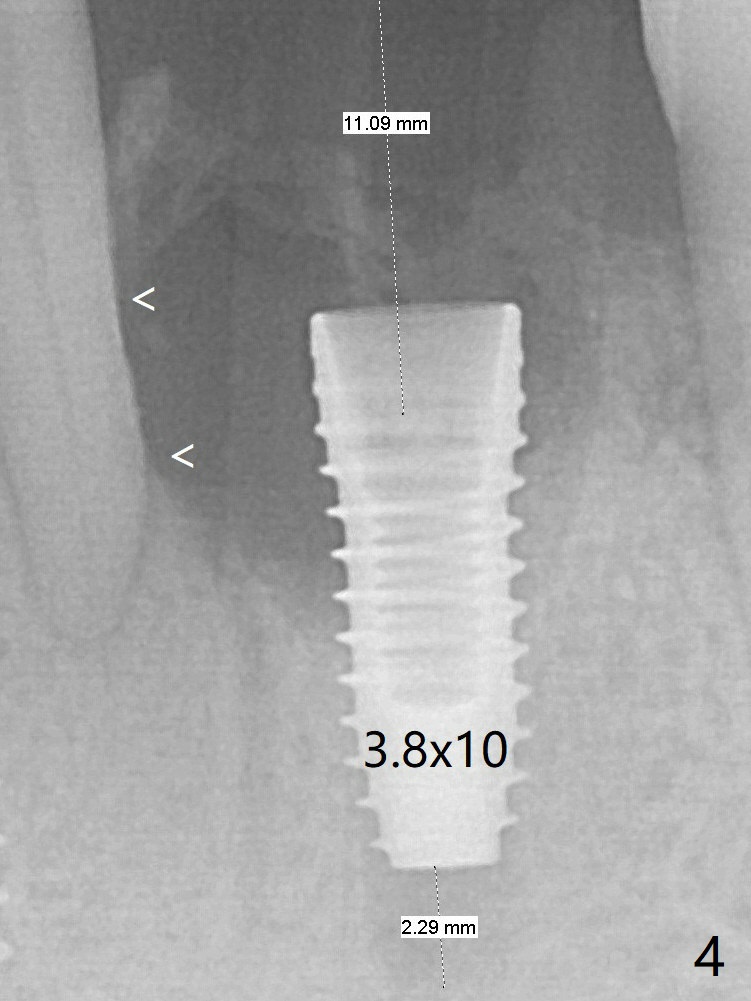

A 3.8x10 mm dummy implant is placed tentatively with an apical space (Fig.4 (the distal root surface of the lateral incisor is denuded (<)). When a same dimension definitive implant is placed with 40 Ncm, it is 2 mm below the lingual gingival margin, whereas 6-7 mm below the buccal one (Fig.5). Vanilla graft is placed before placement of a 5.5x4(5) mm abutment (Fig.6). The root surface of the lateral incisor is covered by the bone graft. Later the abutment is changed to a longer and smaller one (Fig.8) with more of the allograft (*). The short implant is chosen because it has to be placed deep to prevent periimplantitis, especially lingually, in spite of the fact of the unfavorable crown/implant ratio (Fig.4). The diameter of the implant is small so that there is ample space to pack bone graft both buccally and lingually. The majority of the bone graft seems to be in place 8 months postop (Fig.12).